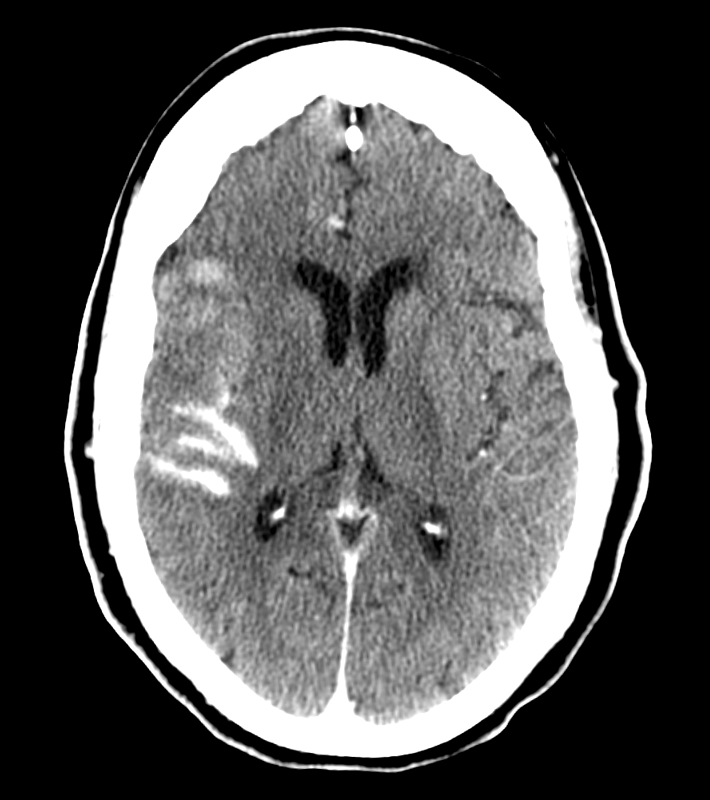

Post CT — some sylvian fissure contrast/blood. Clinically almost back to baseline.